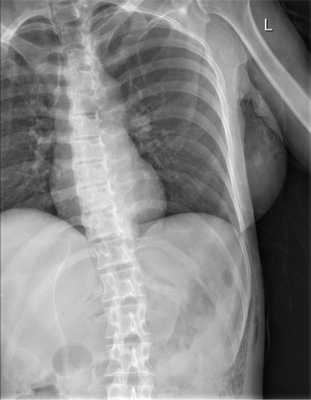

При рентгенологическом исследовании органов грудной клетки и брюшной полости (рис. 1) Рис. 1. Рентгенограмма органов грудной клетки и брюшной полости больной М. при поступлении. выявлена подкожная эмфизема слева от переднего отрезка VI ребра с переходом на брюшную полость. При УЗИ в 5 областях брюшной полости определяется свободная жидкость.